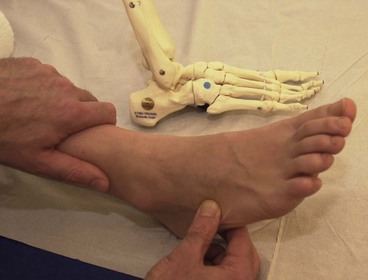

The plantar fascia (plantar aponeurosis) is the thickest fascia in the body. It attaches from a point just behind the medial tubercle of calcaneus and runs anteriorly as five slips. As the slips approach the metatarsal heads, they split into superficial and deep layers (Fig. 12.6A). The superficial layer attaches to superficial fascia beneath the skin, while the deep layer divides into medial and lateral portions to allow the passage of the flexor tendons. Each of the five portions attaches to the base of a proximal phalanx and to the deep transverse ligament.

image

Figure 12.6 Plantar fascia structure and action. (A) Normal tension in fascia. (B) Raising onto the toes tightens the plantar fascia and raises the longitudinal arch.

As the toes dorsiflex and the 1st MP joint is extended prior to toe off, the fascia is wound around the metatarsal head (windlass effect). In so doing the fascia is tightened, shortening the foot and elevating the longitudinal arch (Fig. 12.6B). The combination of these effects supinates the foot and provides a rigid lever for push off. As the foot contacts the ground at heel strike the arch lowers and the foot pronates, becoming a mobile adaptive unit. The plantar fascia is stretched as the foot lengthens.